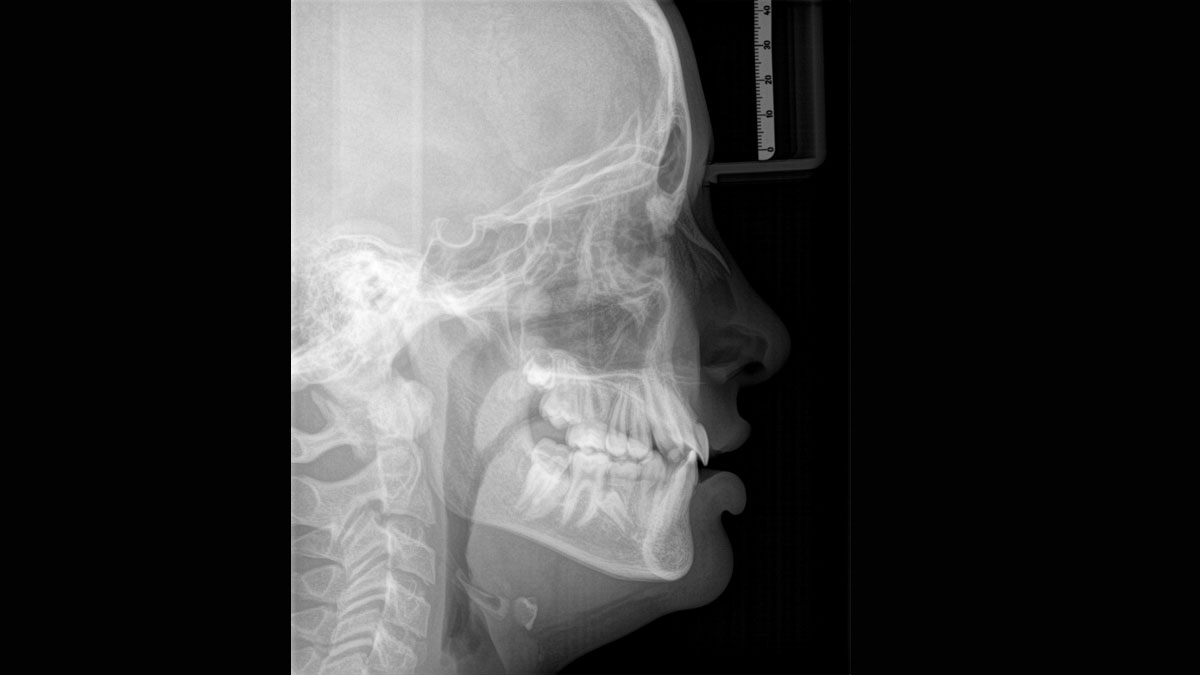

Der 2D/3D Power Performer Orthophos SL ist eine großartige Wahl für alle, die einfach mehr wollen. Der integrierte Direct Conversion Sensor (DCS) wurde für anspruchsvolle Bildqualitätsstandards entwickelt und bietet detaillierte Daten. Der intelligente Autofokus liefert automatisch fokussierte Panoramabilder mit hervorragender Gesamtschärfe. Orthophos SL bietet höchsten Bedienkomfort durch automatische Positionierung, eine anwenderfreundliche, intuitive Bedienung mit dem EasyPad und ein individuell einstellbares Umgebungslicht für ein exklusives Erscheinungsbild.

Der Direct Conversion Sensor erfüllt besonders hohe Standards für die 2D-Bildgebung

Der Autofokus erzeugt aus mehreren tausend Einzelbildern automatisch eine beeindruckende scharfe Panorama-Röntgenaufnahme

Es stehen mehrere Panoramaprogramme für Erwachsene und Kinder (Norm, Bissflügel, Nebenhöhlen usw.) zur Verfügung. Ein Ceph-Arm (links oder rechts) kann zum Zeitpunkt des Kaufs mitgeliefert oder später bei Bedarf nachgerüstet werden

Der Direct Conversion Sensor (DCS) hat den Standard der Panorama-Bildgebung neu definiert. Röntgenstrahlen werden direkt in elektrische Signale umgewandelt – im Gegensatz zu herkömmlichen Systemen gibt es keinen Signalverlust durch Lichtumwandlung, was eine verbesserte Bildgebung ermöglicht. Das Ergebnis sind Bilder mit einer sehr hohen Schärfe, selbst bei niedriger Dosis.

Eine Röntgenaufnahme muss sofort diagnostizierbar sein. Der Autofokus hilft dabei erheblich. Orthophos SL erfasst mehrere tausend Einzelbilder in einem Zyklus und erkennt automatisch scharfe Bereiche, um ein gleichmäßig scharfes Gesamtbild zu erzeugen. Der intelligente Autofokus erfordert keine manuellen Arbeitsschritte vor und nach der Erfassung.